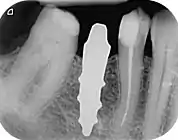

Root analogue dental implant

A root-analog dental implant (RAI) – also known as a truly anatomic dental implant, or an anatomical/custom implant – is a medical device to replace one or more roots of a single tooth immediately after extraction. In contrast to common titanium screw type implants, these implants are custom-made to exactly match the extraction socket of the specific patient. Thus there is usually no need for surgery.

RAIs are custom made to perfectly fit the tooth socket of a specific patient immediately after tooth extraction. Therefore every implant is unique. As an optimized root-form it is much more than a simple 1:1 replica of a tooth. Since it exactly fills the gap left after the tooth is extracted, surgery is rarely needed. The implant can be produced from a copy of the extracted tooth, an impression of the tooth socket, or from a CT scan or CBCT scan.[3] The advantage of a CBCT scan is that the implant can be produced before extraction. With the former methods, it takes one or two days to fabricate an implant.

A root analogue implant can be fabricated from zirconium dioxide (zirconia) or titanium. Successful titanium RAIs have been three-dimensionally printed as porous one-piece implants, using CAD software.[4] However, zirconia is the preferred material, because it is more esthetic in color, with no grey discoloration visible through gums.[5][1]